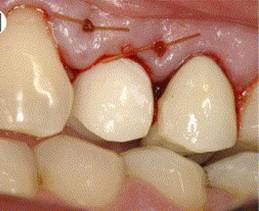

ABUTMENT PLACEMENT

PROSTHESIS

OSTEOINTEGRATE DENTAL IMPLANT SURGERY